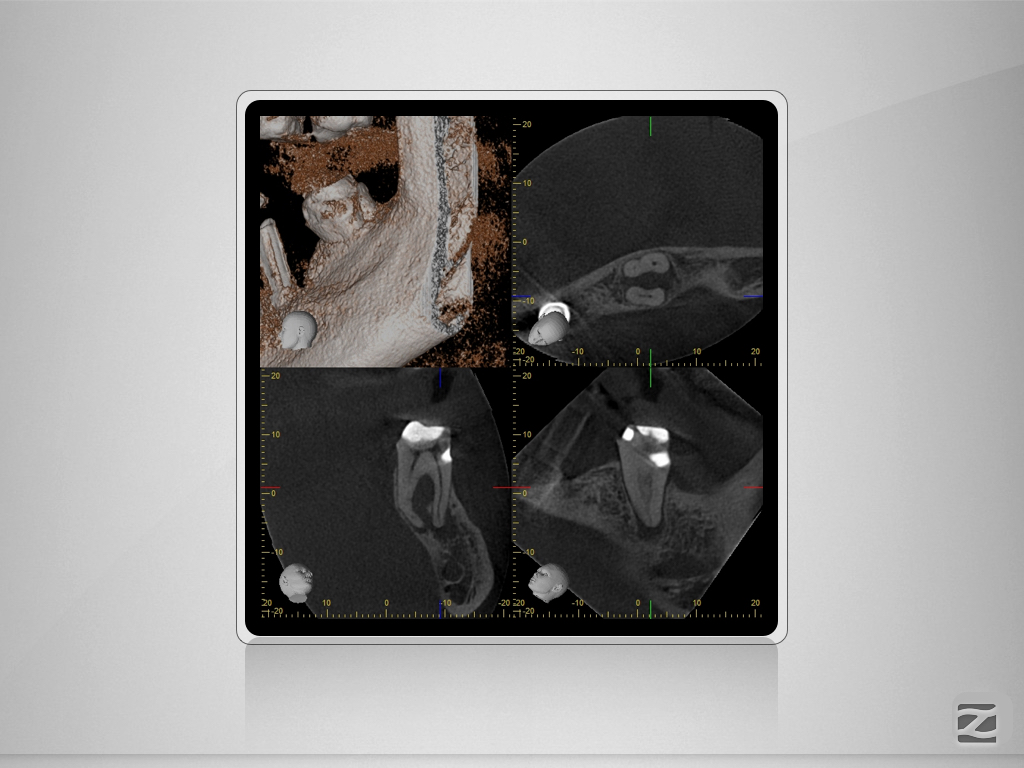

37D.005

2D vs. 3D -Reloaded